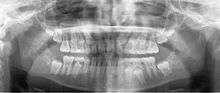

A dental panoramic radiograph, showing the maxilla and mandible, all the teeth including the "wisdom teeth," the frontal and maxillary sinuses, the nasal cavity and the temporomandibular joint and other near by head and neck anatomy. | |

A panoramic radiograph is a panoramic scanning dental X-ray of the upper and lower jaw. It shows a two-dimensional view of a half-circle from ear to ear. Panoramic radiography is a form of tomography; thus, images of multiple planes are taken to make up the composite panoramic image, where the maxilla and mandible are in the focal trough and the structures that are superficial and deep to the trough are blurred.